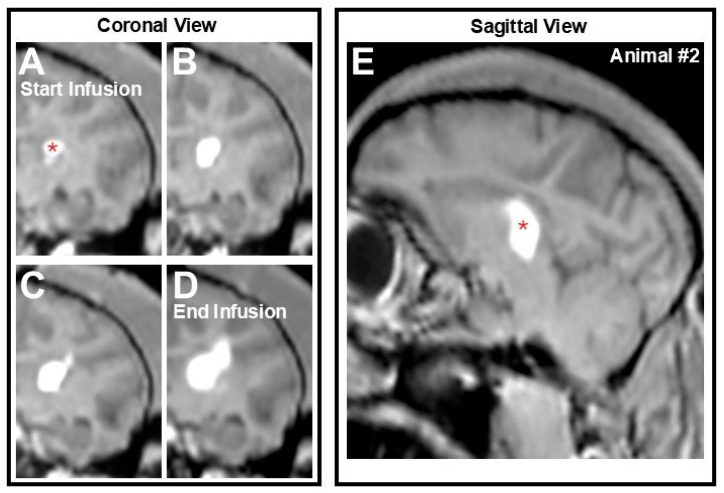

背景:腺相关病毒(AAV)载体是基因治疗的主要平台,但常见的传递途径对远端皮质结构的传播有限,因此直接在丘脑内输注可用于更广泛的转基因分布。在这项初步研究中,我们总结了先前的研究,将丘脑作为实现皮层转基因传播的通道,并展示了使用冷冻荧光断层扫描(CFT)评估绿色荧光蛋白(GFP)生物分布的新数据。我们首次在非人类灵长类动物(NHPs)中,结合磁共振成像(MRI)引导,展示了CFT作为绘制NHP大脑中矢量分布的强大工具的应用。方法:简单地说,使用ClearPoint的导航平台在非洲绿猴中进行单次丘脑输注,以传递含有GFP有效载荷的AAV血清型2载体。利用CFT和组织学分析分别评估左、右半球的转基因生物分布。结果:以亚毫米级的靶精度和最小的误差成功地进行了注射,以最大的输注量实现了~86%的丘脑覆盖率。组织学证实了GFP转基因的存在,在大脑灰质/白质和内囊中信号最强,而CFT可以从输注部位开始三维检测到转基因,并向多个皮质区域扩散。结论:mri引导技术与CFT成像相结合,在NHPs中绘制全脑基因生物分布是可行的。这项概念验证研究弥合了细胞显微镜和mri指导之间的差距,提供了具有临床适用性的疾病和治疗的完整图景。

Background: Adeno-associated viral (AAV) vectors are the leading platform for gene therapy, but common delivery routes show limited spread to distal cortical structures, hence the utility of direct, intrathalamic infusions for broader transgene distribution. In this preliminary study, we recapitulate previous studies targeting the thalamus as a conduit to achieve cortical transgene spread and showcase novel data evaluating biodistribution of a green fluorescent protein (GFP) using cryo-fluorescence tomography (CFT). For the first time in nonhuman primates (NHPs) and coupled with magnetic resonance imaging (MRI)-guidance, we demonstrated the application of CFT as a powerful tool to map out vector distribution in the NHP brain. Methods: Briefly, a single thalamic infusion was performed in African green monkeys using ClearPoint's navigational platform to deliver an AAV serotype 2 vector containing a GFP payload. Transgene biodistribution was assessed in the left and right hemispheres using CFT and histological analysis, respectively. Results: Infusions were successfully performed with sub-millimetric target accuracy and with minimal error, achieving ~86% thalamic coverage with the largest infusion volume. Histology confirmed the presence of the GFP transgene, with the strongest signal in the cerebral gray/white matter and internal capsule, while CFT allowed for the three-dimensional detection of the transgene starting at the site of infusion and spreading to multiple cortical regions. Conclusions: These findings suggest that by combining MRI-guided technology with CFT imaging, it is feasible to map whole-brain gene biodistribution in NHPs. This proof-of-concept study bridges the gap between cellular microscopy and MRI-guidance to provide a complete picture of disease and treatment with clinical applicability.